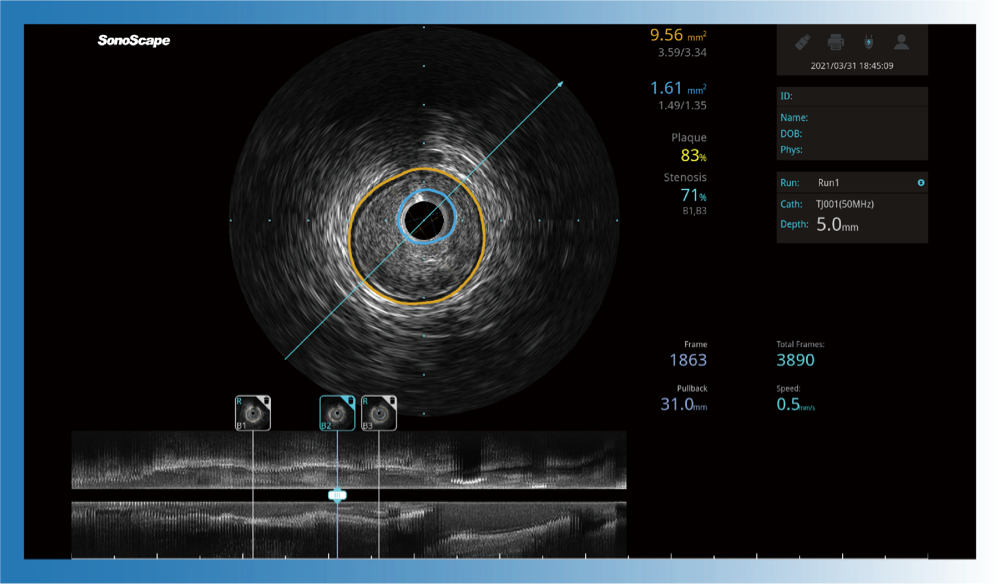

治療前后兩次測量錄像對比

簡化療效評估

一鍵智能描跡,自動測量斑塊負荷、面積狹窄率等指標,準確率高于90%